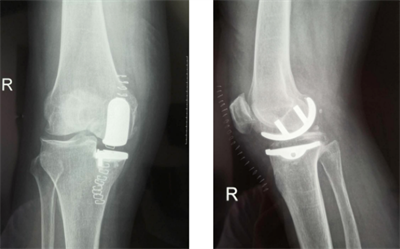

(圖為膝內(nèi)側(cè)單髁置換示意圖)